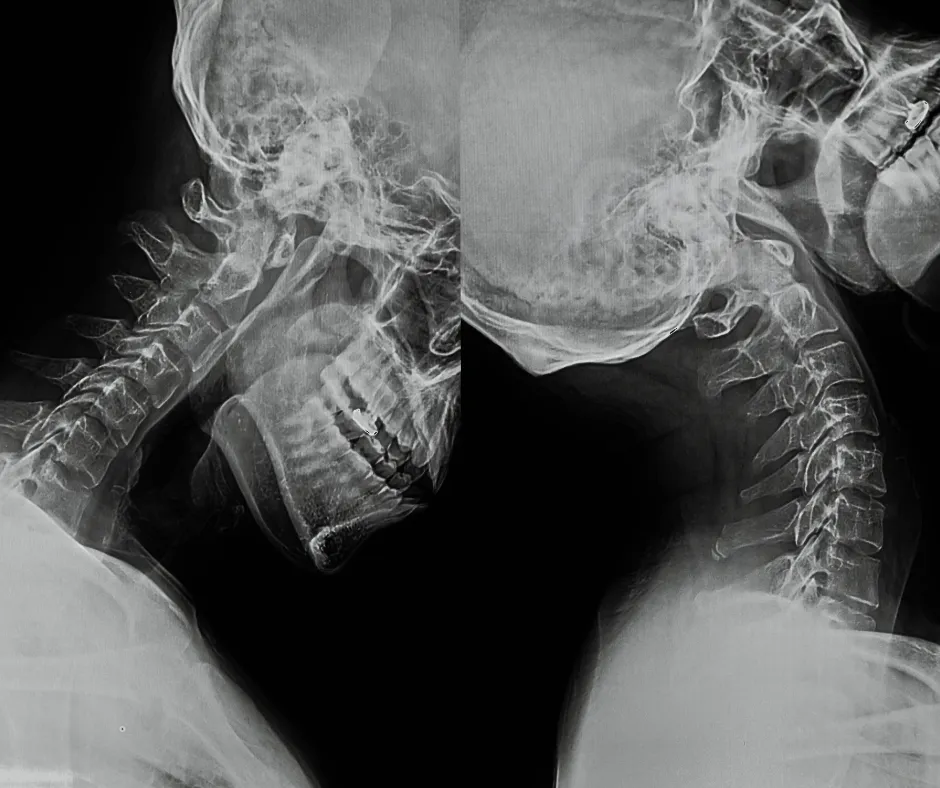

Die Rehabilitation nach einem Schleudertrauma kann ein langer und mühsamer Prozess sein. Der Schlüssel zur Genesung liegt in einer frühzeitigen und umfassenden Behandlung. Zu Beginn wird eine genaue Diagnose gestellt, um den Grad der Verletzung zu bestimmen und mögliche Begleitverletzungen auszuschliessen. Diese kann MRTs oder andere bildgebende Untersuchungen umfassen.